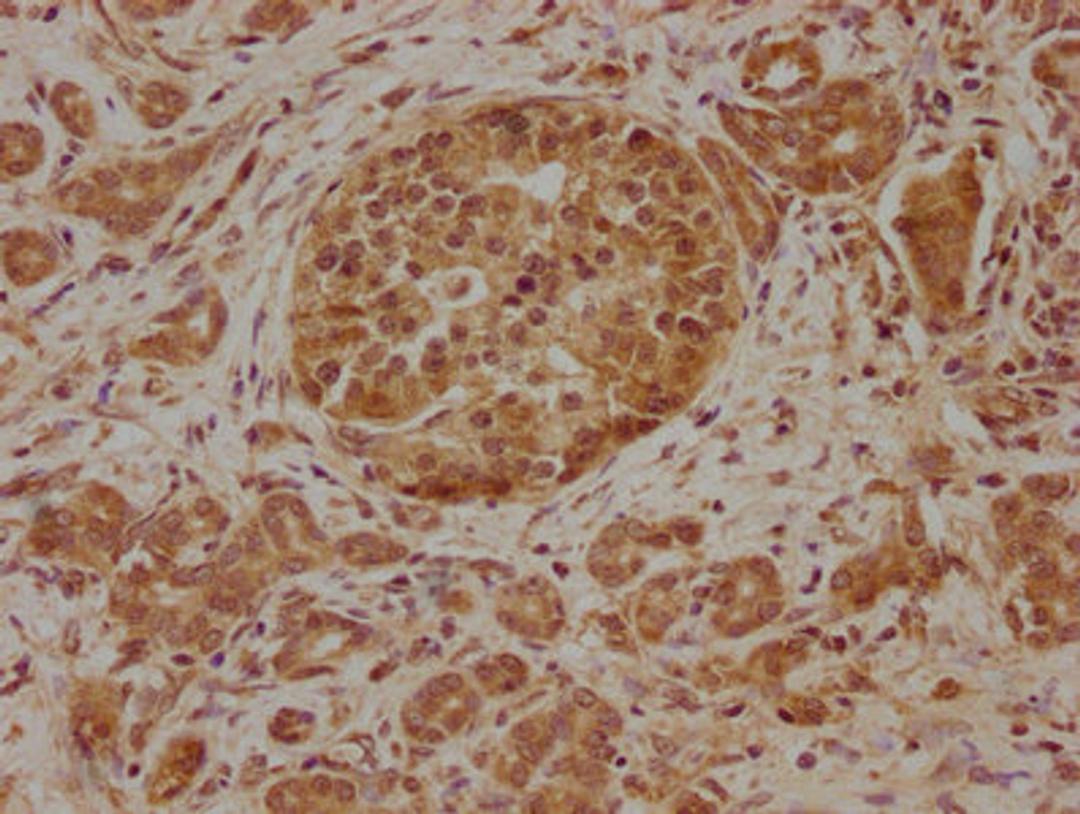

IHC image of CSB-PA891736LA01HU diluted at 1:100 and staining in paraffin-embedded human pancreatic cancer performed on a Leica BondTM system. After dewaxing and hydration, antigen retrieval was mediated by high pressure in a citrate buffer (pH 6.0). Section was blocked with 10% normal goat serum 30min at RT. Then primary antibody (1% BSA) was incubated at 4°C overnight. The primary is detected by a biotinylated secondary antibody and visualized using an HRP conjugated SP system.